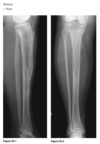

Radiographs of the right tibia and fib-

ula (Figs. 2.21.1 and 2.21.2) show a vague, irregu-

lar linear radiolucency within an area of sclerosis

in the distal third of the tibia (arrowheads). Coronal

T1-weighted MRI of the tibia reveals a serpiginous

region of decreased marrow signal extending over

several centimeters (Fig. 2.21.3, arrows) and a de-

fect in the lateral tibial cortex (curved arrow). Axial

T2-weighted MRI through the same region demon-

strates a bony sequestrum (Fig. 2.21.4, arrowhead)

and increased signal intensity (i.e., marrow edema)

within the tibia. A sinus tract extends through the

lateral aspect of the posterior tibia (white arrow) to

the skin surface anteriorly (black arrow), with edem-

atous changes in the subcutaneous tissues.

Chronic osteomyelitis with a draining

sinus tract